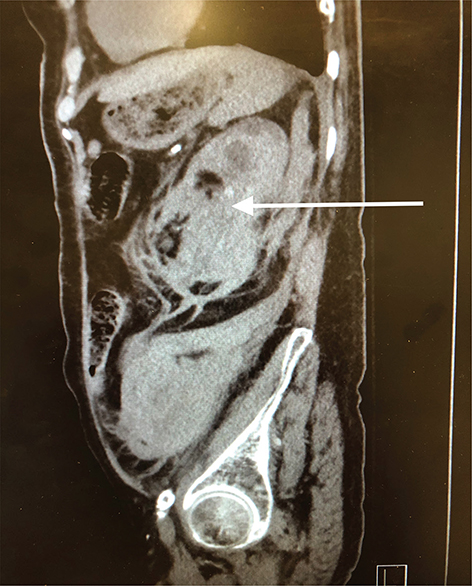

Pathology showed extensive sclerosed glomeruli, marked interstitial inflammation, severe arteriosclerosis, perirenal and renal parenchymal hemorrhage, severe renal artery atherosclerosis, and ACKD. Figurers 1 and 2 show the enlarged left kidney with massive retroperitoneal hemorrhage on CT scan.

Fig 2

Figure 2: Sagital CT image of left retroperitoneal hemorrhage. The arrow shows the extensive left retroperitoneal hematoma with rupture of the left kidney.